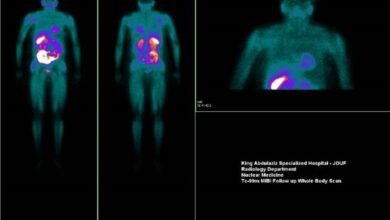

نجاح علاج أول حالة بالنظائر المشعة في مستشفى الملك عبدالعزيز التخصصي بالجوف

نجح مستشفى الملك عبدالعزيز التخصصي بالجوف في علاج أول حالة سرطان لغدة درقية بقسم الطب النووي المستشفى.

وأبانت صحة الجوف أنه تم علاج مريضة حضرت للقسم لاستكمال علاجها باليود المشع، وذلك بعد إجراء استئصال جراحي لورم سرطاني من الغدة الدرقية ، حيث تم إجراء مسح ذرى باليود المشع على كامل الجسم, وتبين وجود بقية الورم على الغدة وبعدها تم تحديد الجرعة العلاجية المطلوبة للمريضة بناءً على البيانات والمعلومات الطبية الخاصة بها، حيث تم إعطاءها جرعة علاجية من اليود المشع, وخضعت للمتابعة بعد 6 أشهر من الجرعة.

وأضافت أن المسح الذري أثبت – ولله الحمد – الشفاء التام للأجزاء المتبقية من الغدة الدرقية، مع عدم اكتشاف أي بؤر سرطانية لهذا الورم في الجسم, وتم تأكيد ذلك بتحاليل دلائل الأورام الخاصة بالغدة الدرقية.